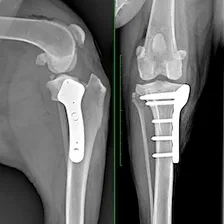

TPLO

TPLO is considered the gold standard for managing cranial cruciate ligament tears in dogs. Yielding better outcomes with fewer complications, it is the most reliable & predictable surgery available and is recommended by most orthopaedic surgeons.